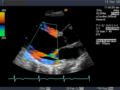

Die Aussagekraft der Sonografie kann erheblich durch die Anwendung des Doppler-Effekts erhöht werden. Man unterscheidet eindimensionale Verfahren (Pulsed-Wave-Doppler, Continuous-Wave-Doppler, auch als D-mode bezeichnet) von zweidimensionalen, farbkodierten Anwendungen (Farbdoppler – F-mode). Die Kombination B-Bild mit Pulsed-Wave-Doppler (PW-Doppler) nennt man auch Duplex.[4]

Doppler-Verfahren werden benutzt zur Bestimmung von Blutfluss-Geschwindigkeiten, zur Entdeckung und Beurteilung von Herz(klappen)fehlern, Verengungen (Stenosen), Verschlüssen oder Kurzschlussverbindungen (Shunts).

Bei der farbkodierten Doppler-Sonografie wird für einen großen Bereich eines konventionellen Ultraschallbildes (Color-Window) die örtliche Doppler-Frequenz (= mittlere Flussgeschwindigkeit) und deren Schwankungsbreite bestimmt. Damit möchte man die Turbulenz der Strömung abschätzen. Aufgrund der statistischen Bewegungen der Streuteilchen ist die Schwankungsbreite der Fließgeschwindigkeit jedoch stets größer als die Turbulenz. Das Ergebnis wird in Falschfarben auf dem B-Bild überlagert, also in Farbtönen von rot und blau für verschiedene Blutgeschwindigkeit und grün für Turbulenz. Hierbei steht üblicherweise die Farbe Rot für Bewegung auf den Schallkopf zu, während mit blauen Farbtönen Flüsse weg von der Sonde codiert werden. Bereiche der Geschwindigkeit 0 werden durch die Elektronik unterdrückt.

-

Anwendung des Doppler-Verfahrens bei einer Herzuntersuchung: Mitralklappeninsuffizienz -